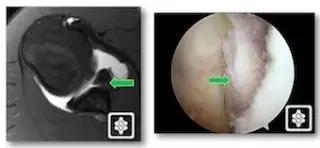

3. 骨性 Bankart 损伤(Bony Bankart lesion)

下盂肱韧带盂唇复合体损伤同时伴有关节盂前下方的撕脱性骨折。由于关节盂前下方的骨质缺损,可以导致梨形的肩盂变为「倒梨形」结构,出现关节不稳的主要因素。

骨性 Bankart 损伤的 MR(左)和 CT(右)(来源:ShoulderDoc)

骨性 Bankart 损伤的 MR(左)和关节镜图(右)(来源:ShoulderDoc)